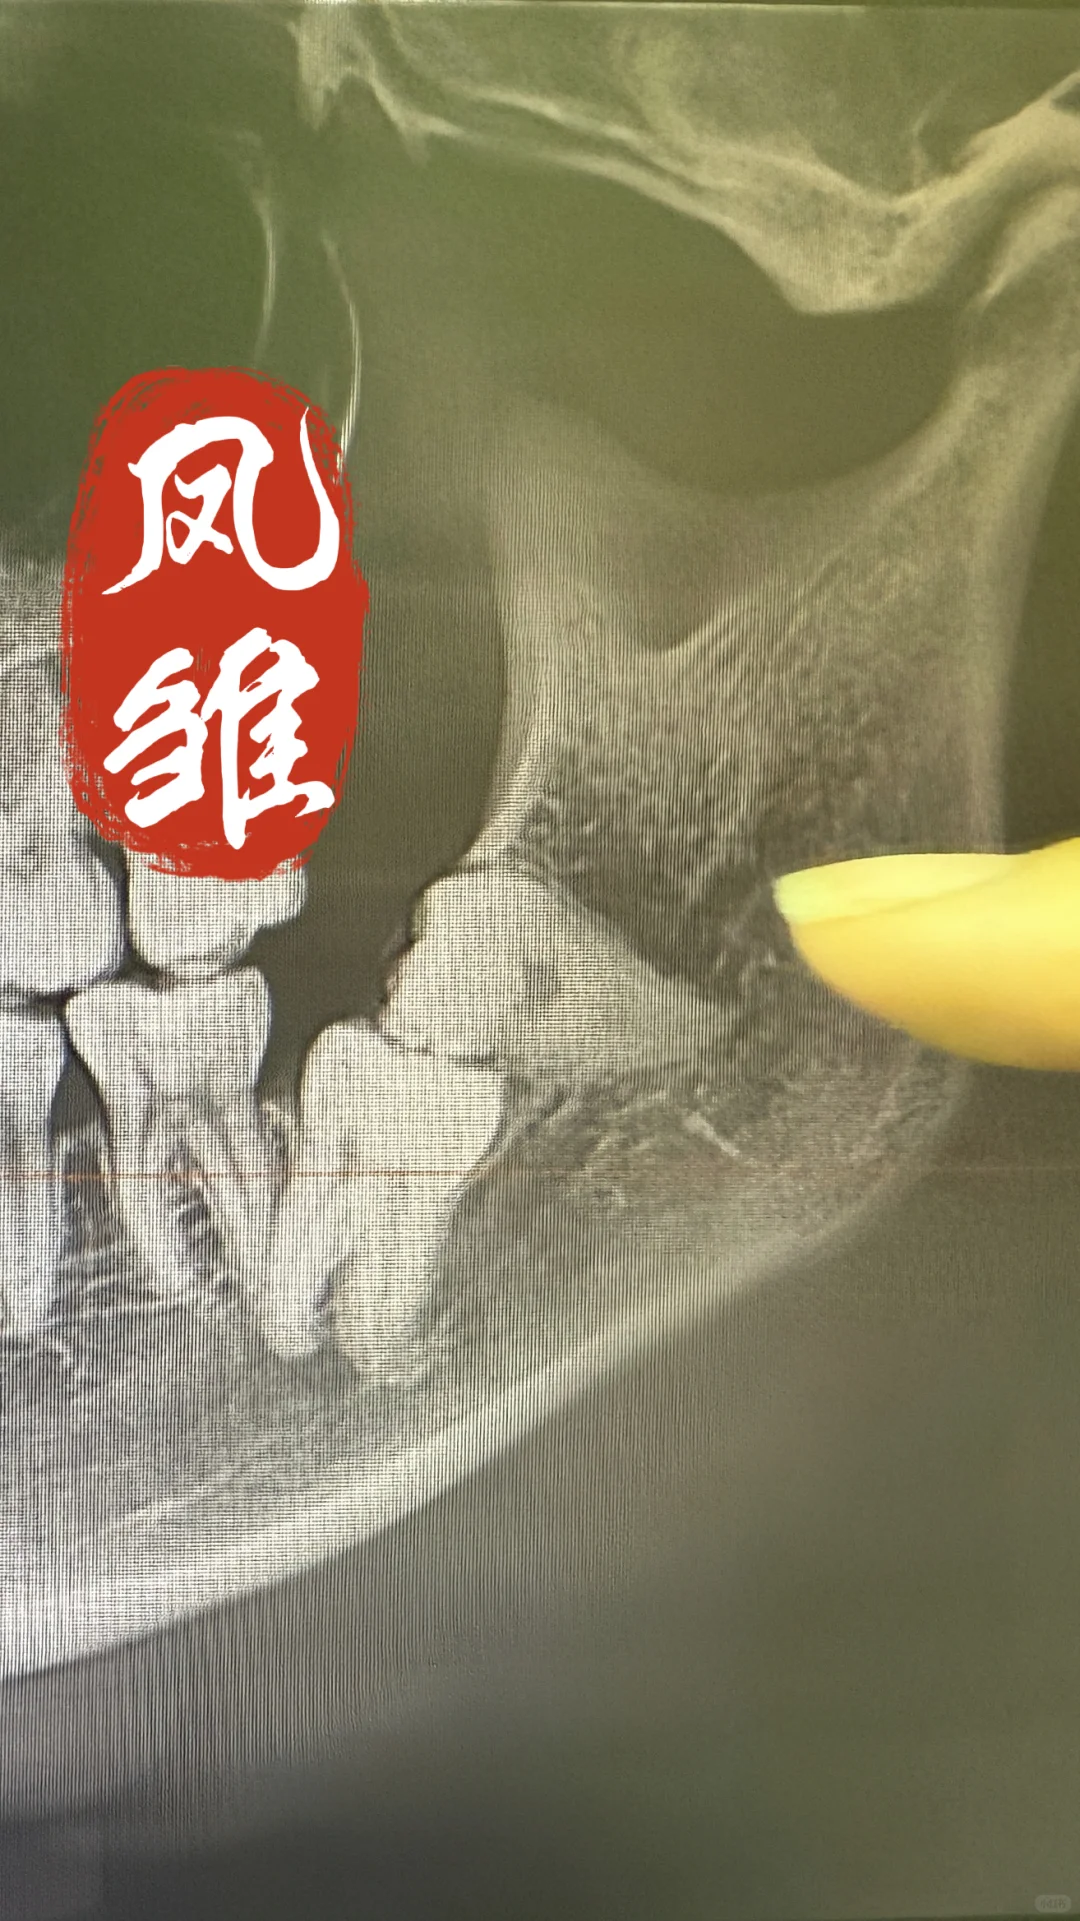

[哇R]图一去右下颌骨内含牙囊肿,牙齿倒置长再骨头里面~ [哇R]图二去左下第二磨牙埋伏,智齿又压在磨牙上面,一起阻生在骨头里面~ [失望R]锤哥一天能遇到这两位卧龙凤雏,也是我职业生涯中浓墨重彩的一笔啊